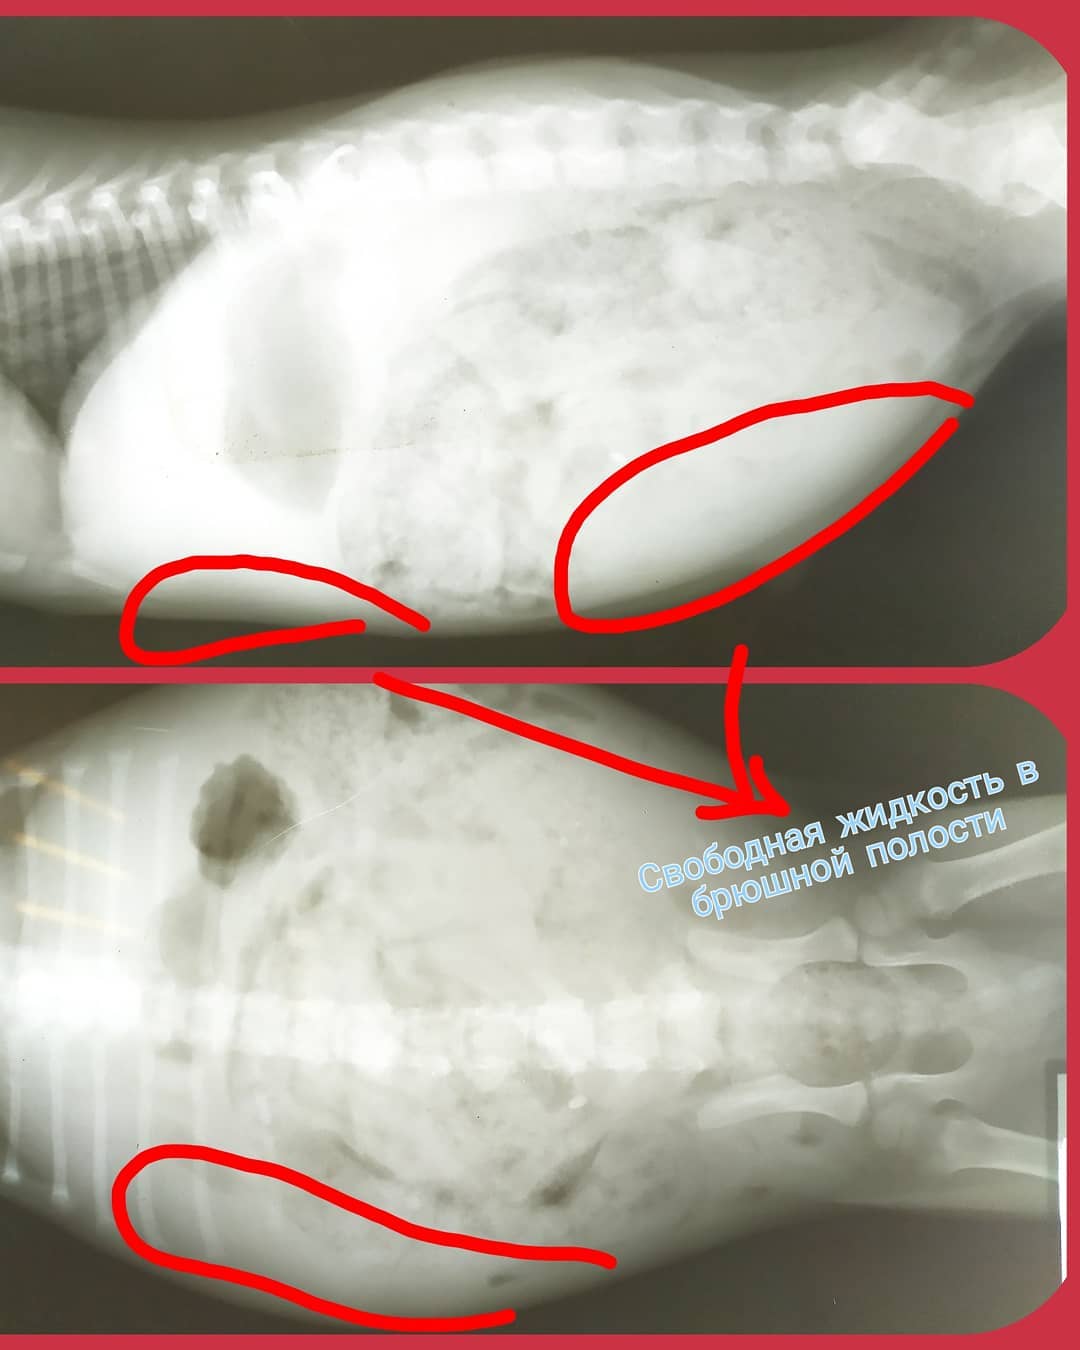

При надходженні до клініки у щеня спостерігалися симптоми діареї з кров'ю, дегідратація, втрата ваги, анемічність слизових. Черевна порожнина збільшувалася в обсязі, тварина ставала млявою, малорухливою.

+ рентген та УЗД

Виявлено: запальний процес у кишечнику, гіпоальбумінемія, гіпокальціємія, анемія.